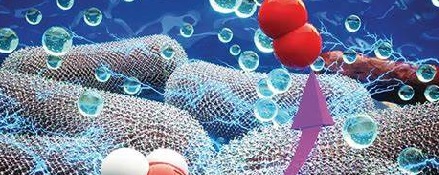

In these studies, scientists in advance, tracked tiny pieces of microplastics as they moved through the brain blood vessels of mice, and watched that some of them became stuck. Then, and for the first time, scientists used real-time imaging to track tiny pieces of microplastics as they moved through the brain blood vessels of mice.

In these studies, scientists in advance, tracked tiny pieces of microplastics as they moved through the brain blood vessels of mice, and watched that some of them became stuck. Then, and for the first time, scientists used real-time imaging to track tiny pieces of microplastics as they moved through the brain blood vessels of mice.

As detailed in a recent paper published in the journal Science Advances, first spotted by The Guardian, the project made an alarming discovery: some of the pieces of plastic were becoming stuck, causing more chunks to accumulate behind them in what one of the researchers likened to a “car crash.”

“This revelation offers a lens through which to comprehend the toxicological implications of microplastics that invade the bloodstream,” the paper reads.

The paper’s authors gave mice water that was laced with fluorescent-coated polystyrene, allowing them to use

an imaging technique called “two-photon microscopy” to track how they moved into the mice’s brains.

When encountering tight bends within the organs’ cortex vessels, the tiny pieces of polystyrene appear to have gotten absorbed by immune cells, creating unusually-shaped cells that then become stuck.

Some of these blockages became unstuck by themselves over time. However, the finding that stuck pieces of microplastics can get lodged in the first place and reduce blood flow is concerning.

“Environment microplastics might be another important risk factor for cardiovascular disease and received scant attention so far,” the researchers wrote. “Our findings provide a mechanistic explanation for tissue damage induced by microplastics, particularly regarding their effects on vascular obstruction.”

“Environment microplastics might be another important risk factor for cardiovascular disease and received scant attention so far,” the researchers wrote. “Our findings provide a mechanistic explanation for tissue damage induced by microplastics, particularly regarding their effects on vascular obstruction.”